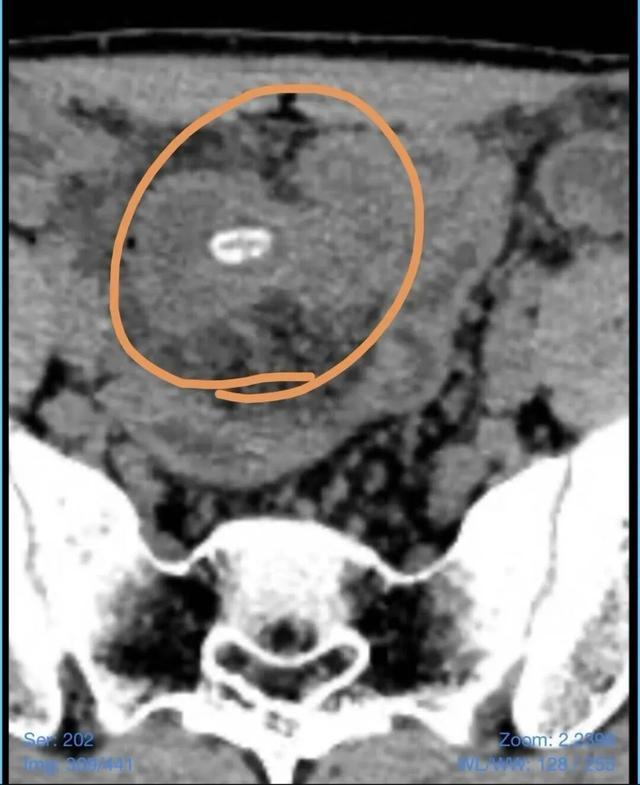

几天前,正在就读大学的小李突然感到右下腹持续性疼痛,有时甚至疼得直不起腰,无法正常活动。家人立即将他送往附近医院就诊。腹部CT检查提示,小李的阑尾略增粗,同时小肠内有一个疑似坚果的异物影像。结合症状,接诊医生初步诊断为“阑尾炎”,并给予了抗感染保守治疗。然而,经过两天的输液治疗,小李的腹痛不仅没有丝毫缓解,反而愈演愈烈,甚至出现了发热、恶心等新症状。焦急万分的家人将其转诊至扬州市妇女儿童医院寻求进一步诊治。

扬州市妇女儿童医院外科副主任医师夏伟接诊后,立刻对小李进行了细致检查和详细病史询问。在翻阅外院CT报告并反复追问下,一个关键细节浮出水面:小李回忆起,发病前几天曾吃过瓜子,并且他平时就有直接吞咽瓜子的习惯,很少咀嚼。结合患者右下腹持续加重的疼痛、腹部明显的压痛反跳痛等体征,以及CT提示的小肠内异物,夏伟凭借丰富的临床经验,敏锐地意识到这并非普通的阑尾炎。“患者的症状虽然很像阑尾炎,但抗感染治疗无效,这提示我们病因可能更为复杂。”夏伟分析道,“我们高度怀疑是瓜子导致了‘美克尔憩室’这一先天性肠道畸形部位的穿孔。”